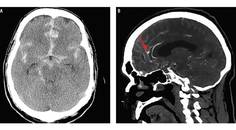

Vasculitis Presenting as a Hypertensive Crisis With Back Pain

Julia Blanter, MD; Michael Colin, MDJulia Blanter, MD; Michael Colin, MD